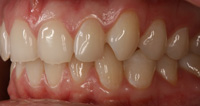

Lingual Veneers - Why? To restore worn-away enamel from acid erosion due to eating disorders.Lingual veneers are veneers that are placed on the inside, or lingual, surface of the front teeth. Rather than remove any healthy enamel from the remaining front and back sides of the teeth to do crowns, lingual veneers offer a conservative alternative for those who have experienced acid erosion, or tooth wear, of the lingual surfaces due to the detrimental effects of eating disorders such as bulimia. The goal is to build up and restore worn away teeth while preserving as much of the natural, beautiful and healthy tooth structure as possible. This strengthens and reinforces the tooth from further damage and drastically reduces sensitivity so a healthy diet and lifestyle can be resumed. Professional dental help for bulimia It is important to seek dental care if you have bulimia and to openly share with the dentist what is happening. Many dentists are caring professional people who understand the problems with bulimia and want to help. Without the dentist's help, the dental consequences of your bulimia can be severe. Dr. Berland can usually provide all of the dental services needed to restore the bulimic patient back to good dental health in a confidential and private manner. Additionally, Dr. Berland can help a bulimic patient manage the condition so that, even if they are continuing to have problems, the dental consequences of bulimia are lessened or eliminated. The Dallas Dental Arts services can be specially arranged for a bulimic patient so that all needed dental treatment can be intensively completed in a short period of time. This makes it possible for patients from out of town to complete their desperately needed dental care confidentially and in as few visits as possible. The Dallas Dental Arts can also assist in obtaining the funds for this care so everything that needs to be done can be completed. For more information on financial assistance, please click here. Dr. Berland has successfully cared for many patients suffering from bulimia and would be pleased to meet with you in a confidential consultation. Here, You can privately discuss your choices in dealing with your bulimia. Dr. Berland understands that you are struggling with bulimia and that it may take time to deal with the consequences of your bulimia. Privately speaking with Dr. Berland can be your first step in conquering your bulimia. Please consider calling (214)999-0110 and scheduling a consultation. You do not have to say why you are visiting, just that you would like a private consultation. If calling for an appointment is too embarrassing, you can first email Dr. Berland at drberland@dallasdentalspa.com or you can schedule a consultation and privately email him to let Dr. Berland know that you wish to talk about your bulimia. This young lady came to our office looking for a way to improve her smile, self-image and most importantly, her health. As a recovering bulimic patient, she had endured years of damage to her enamel from her previous history of eating disorders. In her case, the erosion wore all the way through her enamel and even into the soft, sensitive inner tooth layer, the dentin. She sought us out to find a way to restore her smile without further compromising the fragile condition of her teeth. Other dentists discussed filing her already thinned down teeth further and "strengthening" them with porcelain crowns. Our approach was completely different. Why take away more when you don’t have much to begin with? We recommended she try lingual resin veneers (on the backside of her teeth) followed by cosmetic one-stop bonding on the front and especially the edges of her teeth. This is a completely noninvasive and a purely additive procedure. She would be adding strength to her teeth, fortifying them rather than removing any of her remaining enamel, thereby reinforcing her teeth, improving her dental condition and creating the beautiful, yet natural, smile she desired. When the patient heard of this conservative treatment alternative, it made sense to her to preserve her teeth to maintain her health and restore her smile. Not only were the back sides of her teeth built out, length was added to replace what was worn over the years for a more youthful smile. After the no-shots, no-drilling, and no-pain appointment, her teeth were no longer sensitive to sweets, hot or cold. The patient was very pleased with her results. She not only gained a beautiful, new smile, but she also had a renewed confidence in herself and a reassurance of a healthier smile – and that means a healthier lifestyle as well! With all the focus of the media on diets, exercise equipment and personal care products, people are more concerned with their appearance and physical health than ever. In an effort to meet today's standard of beauty and "health", many people are quick to try the newest crash diet fad without ever realizing that this may, in fact, be the incorrect way to diet. These crash dieters who excessively fast, or try every new trend, tend to have a lack of, or decrease in certain vitamins, most notably Vitamins D, B-12 and calcium. They also tend to lack certain minerals and proteins in their diets. These are very important vitamins especially for the health of the teeth and gums. What can occur is that dieters tend to have a diet high in fruits which may contain a high content of natural sugars. These sugars tend to decay and erode the enamel of the teeth. Mints, used to combat the bad breath associated from Ketosis caused by an unbalanced protein diet and "so-called" Power Bars can further decay the teeth. Dieters also tend to take diet pills that may cause a decrease in saliva flow as a side effect. This decrease in saliva flow tends to increase the acid levels in the mouth which may cause an increased level of cavity formation. Antidepressants and decongestants have the same effect. Dr. Berland cares about the health and well-being of his patients. If you are currently on a diet that restricts certain food groups and/or you are taking a supplement or prescription diet aid, your oral health may compromised and in need of attention. Click here to see an example of the effects of eating disorders on your teeth. Please discuss with Dr. Berland at your next appointment any of these changes in diet or methods of weight control and any problems or discomfort you may be experiencing in your teeth and gums. Dr. Berland has many conservative measures to prevent and alleviate these conditions. Preventing a dental situation before it becomes a problem can save not only your teeth-- but, discomfort, time, money and your health. |